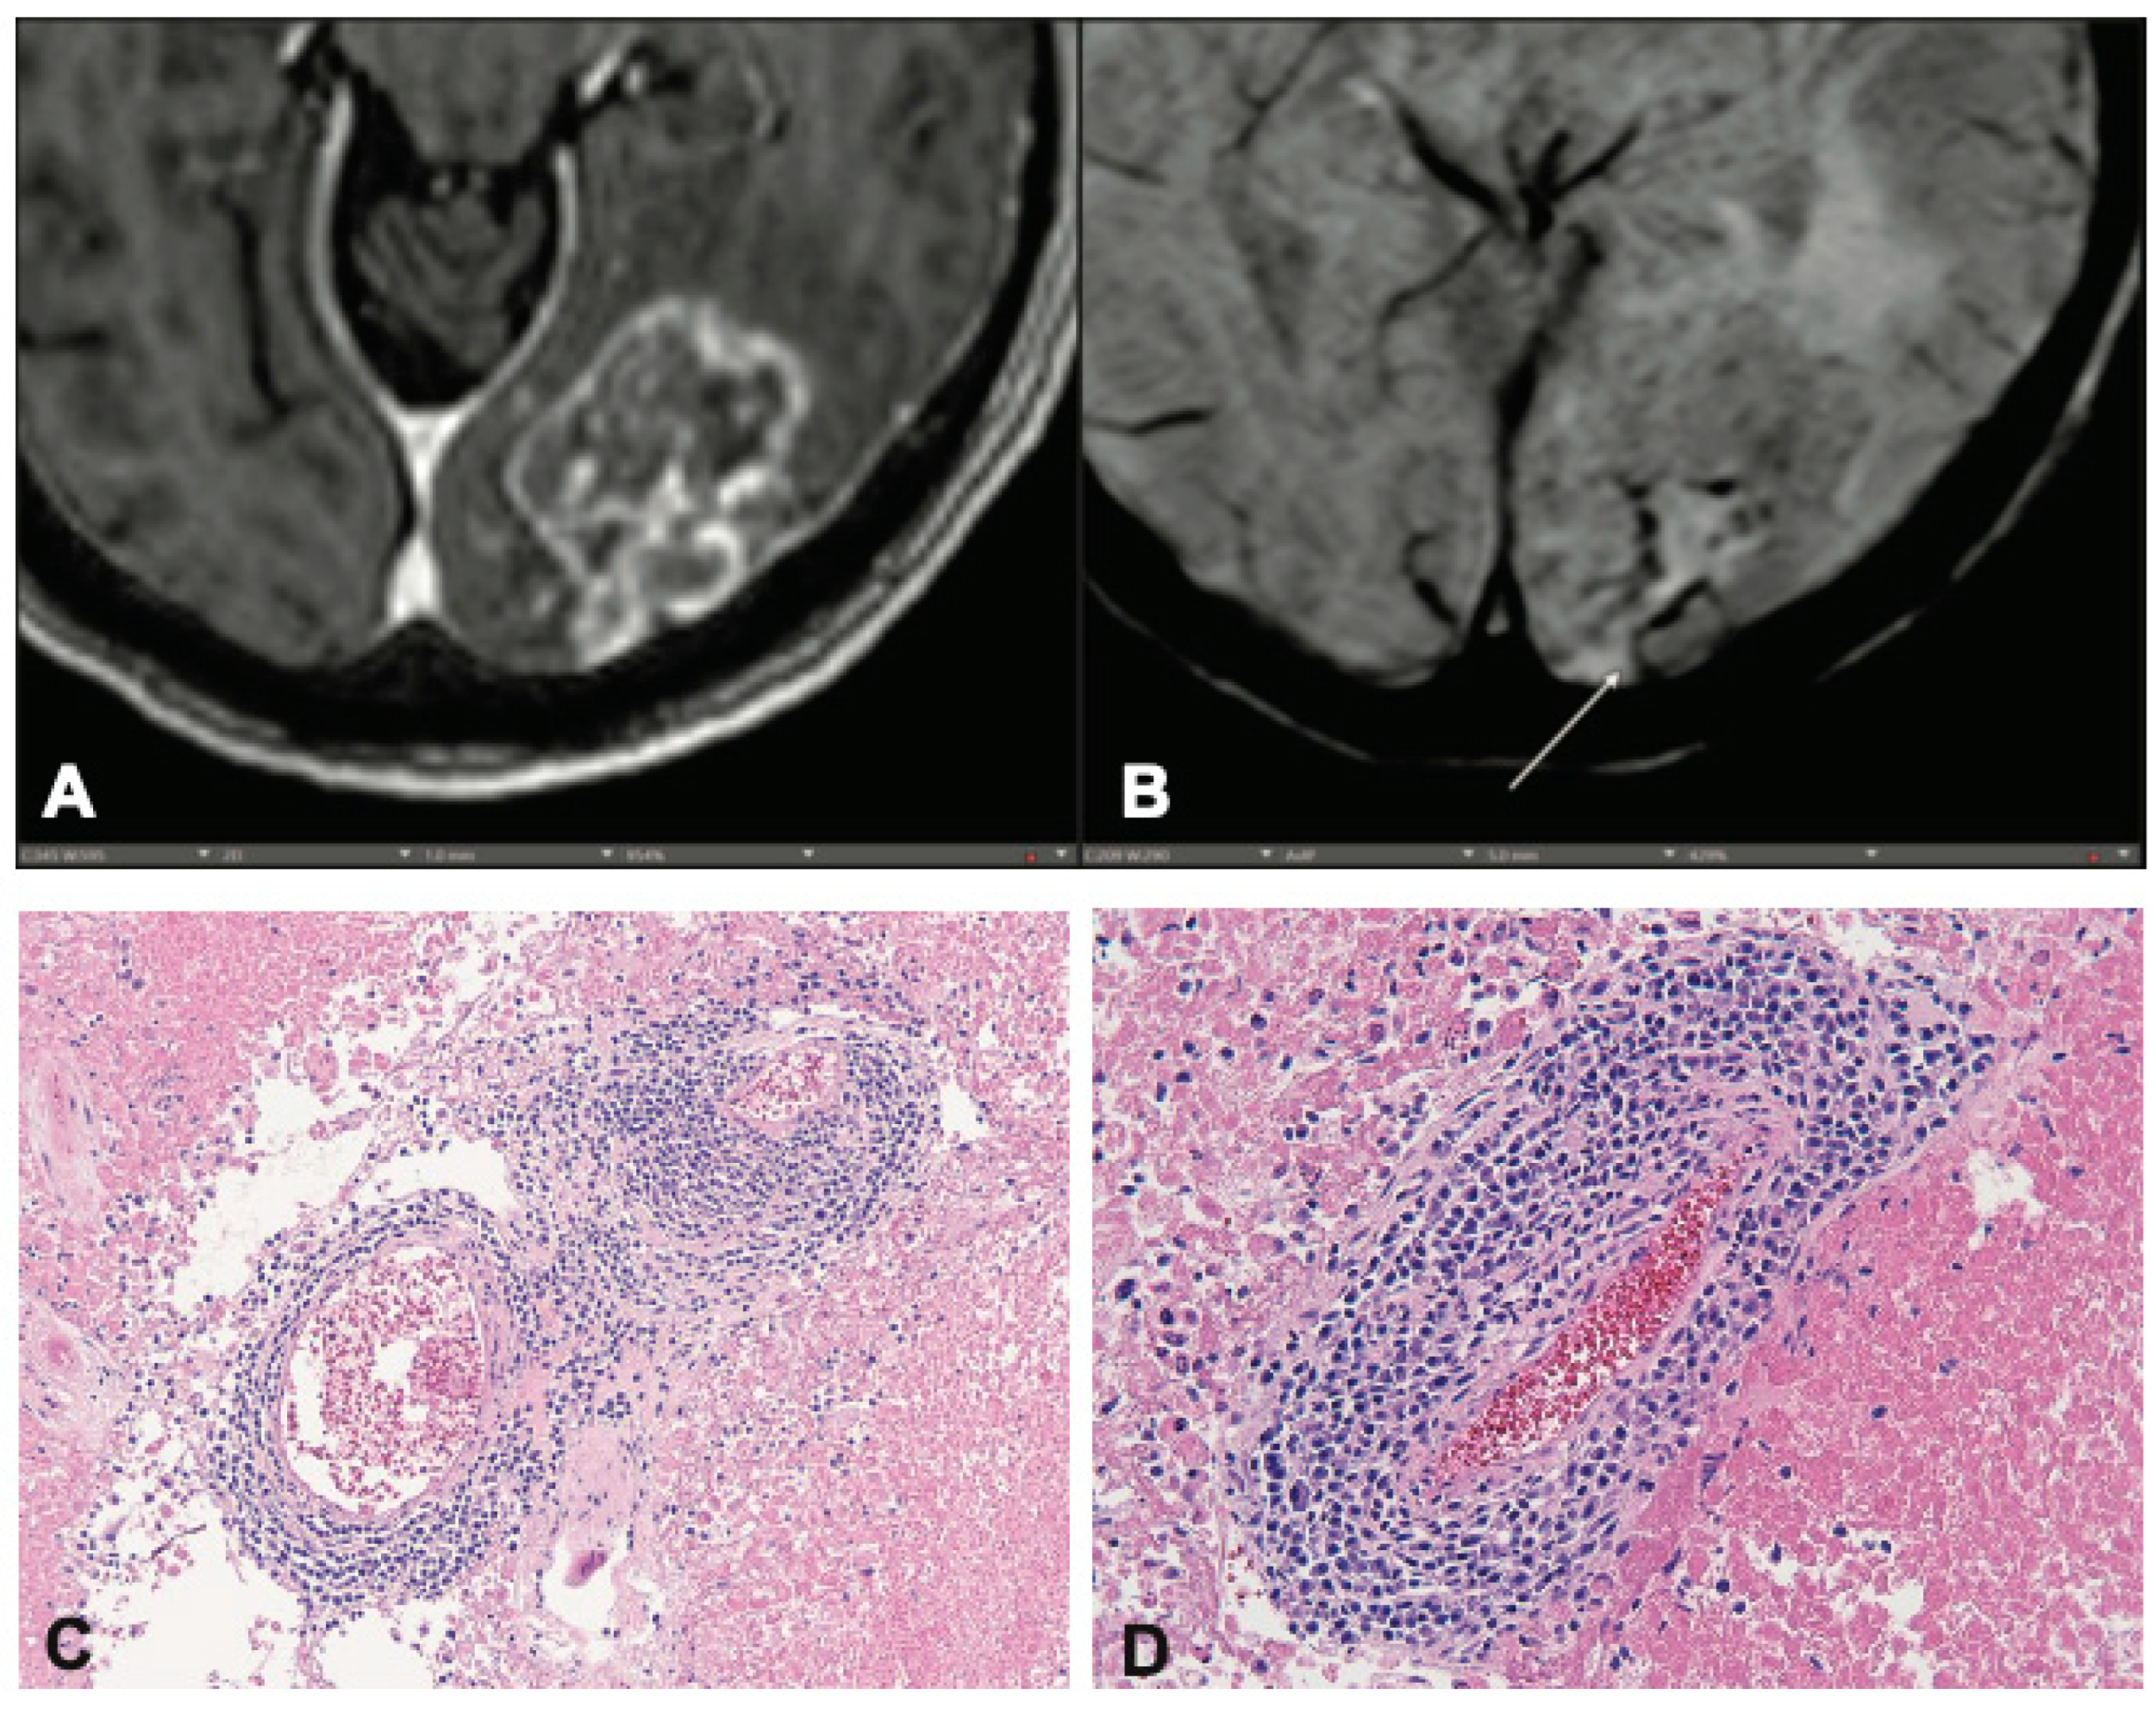

To understand the biologic relevance of the CVS in the context of post-RT disease, we retrospectively identified patients whose records indicated that there was residual fixed tissue available for additional histologic staining. Of these, 9 had sufficient tissue for processing and staining steps as determined by our Pathology Department. We found that, regardless of diagnosis of RN or TP, patients with a CVS (Figure 2a, b) had a corresponding presence of perivenular immune infiltrate (Figure 2c, d). This immune infiltrate was not present in patients without CVS. Hematoxylin & Eosin-stained slides showed stigmata of radiation induced changes, such as vascular hyalinization, necrosis and/or the presence of few residual tumor cells. Immunohistochemical stains highlighted individual cell types and demonstrated the presence of leukocytes (CD45) (Supplemental Figure S3a), T-lymphocytes (CD3) (Supplemental Figure S3b), and macrophages (CD68) (Supplemental Figure S3c), or in a diffuse intraparenchymal distribution pattern and occasionally as small perivascular accumulation (Supplemental Figure S3d).

Figure 2. Hematoxylin and Eosin-stained slides reveal radiation-induced changes such as vascular hyalinization, necrosis, and the presence of a few residual tumor cells. Immunohistochemical stains highlight individual cell types, demonstrating (A) leukocytes (CD45), (B) T-lymphocytes (CD3), and (C) macrophages (CD68). (D) These cells are found either diffusely within the parenchyma or occasionally as small perivascular accumulations.